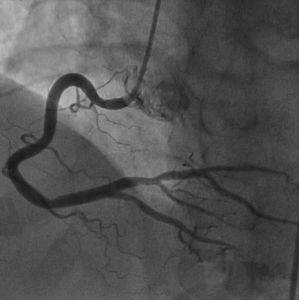

冠狀動脈造影是診斷冠心病的一種有效方法。將導管經大腿股動脈或其它周圍動脈插入,送至升主動脈,然後探尋左或右冠狀動脈口插入,注入造影劑,使冠狀動脈顯影。能較明確地揭示冠狀動脈的解剖畸形及其阻塞性病變的位置、程度與範圍。冠狀動脈造影是目前唯一能直接觀察冠狀動脈形態的論斷方法,醫學界號稱其為“金標準”。冠狀動脈造影術的死亡率約在0.11%-0.14%,心肌梗死率約在0%-0.06%;左冠狀動脈主幹病變患者的心肌梗死與死亡率均約在3.0%。

冠狀動脈造影是一種非常安全、有效的檢查手段。無須開刀,在局部麻醉下僅將特殊的導管經大腿股動脈或上肢橈動脈穿刺後插至冠狀動脈開口,選擇性地將造影劑注入冠狀動脈,記錄顯影的過程。檢查一般只需要15~30分鐘,術後病人平躺12~24小時後就可下地活動,不受年齡、性別限制,絕大部分病人都能接受。現已逐漸成為一項較常規的檢查手段。